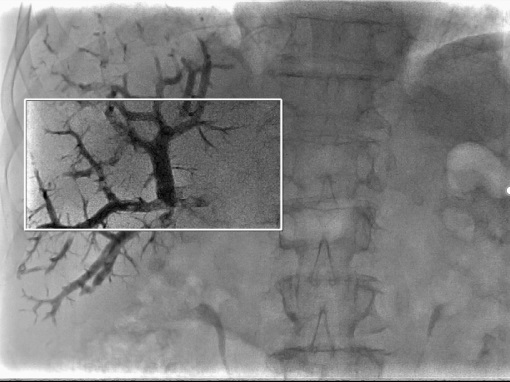

Програмне забезпечення Embolization Plan використовується для аналізу 3D-зображень. Це дозволяє виокремити пухлину і судини, що кровопостачають її, та візуалізувати для процедури трансрадіальної хіміоемболізації (TACE):